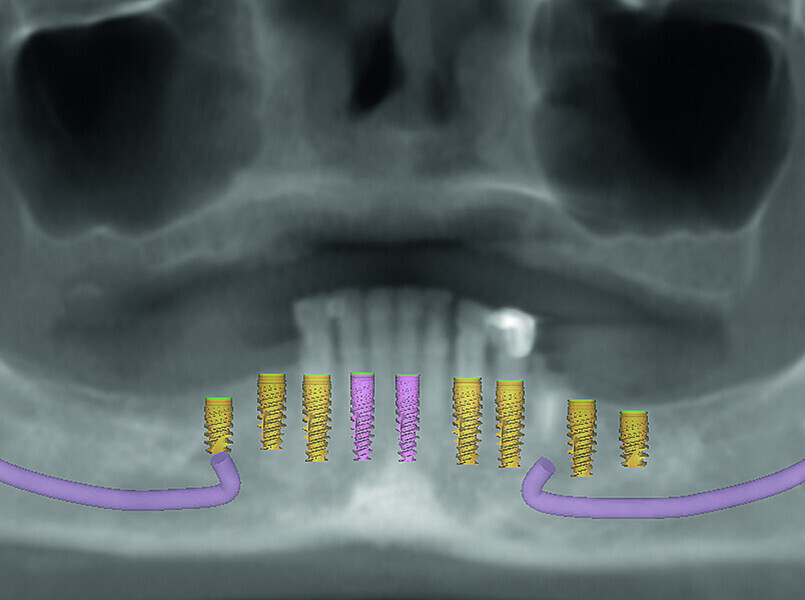

Fig 6 Analyse dento-faciale du traitement implantaire proposé dans l’arcade mandibulaire